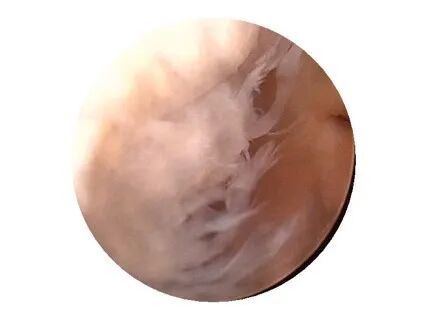

在全身187个滑膜关节中,膝关节滑膜是面积最广、最复杂的滑膜,滑膜腔也最大。

膝关节滑膜的特点:

• ①滑膜面积最大,分泌滑液最多;

• ②脂肪垫及绒毛数量最多,也最大;

• ③与周围结构,特别是肌腱明显分开;

• ④滑膜形成许多囊状隐窝,其中5个位于关节腔前面,4个位于关节腔后面,从而使滑膜腔容积大大增加,成为人体关节腔最大的关节;

• ⑤滑膜面积是全身最大者,并且形成皱襞以适应膝关节的各种运动